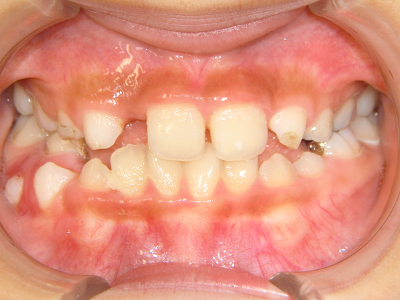

小児矯正について

歯並びの相談に来られるお子様は、口呼吸をしているケースが多く、これが歯並びに大きな影響を与えています。

- 口呼吸をしている

↓ - 舌の位置が悪くなる

↓ - 頬の圧力が上の歯列にかかりやすくなる

↓ - 上あごが狭くなる

↓ - 下あごが狭くなる・下あごの位置が悪くなる

↓ - さまざまな不正咬合が生じる

ないき歯科クリニックでは、上あごの成長不足を補い、鼻呼吸を獲得しつつ歯列を整え、将来のお口をより健康な状態にすることをゴールに定める矯正治療をおこなっています。